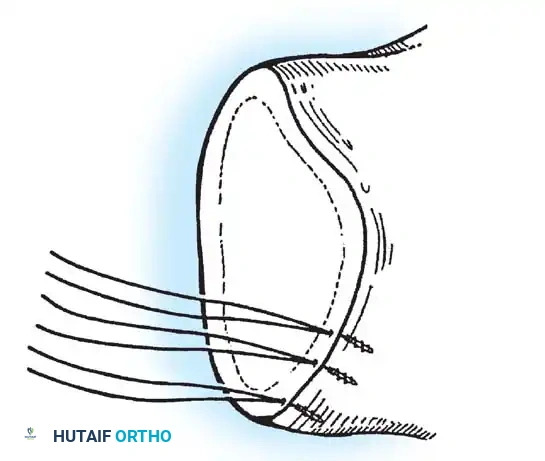

- Anchor Placement: Suture anchors (typically 3 to 4) are placed along the articular margin of the anteroinferior glenoid (from the 5:30 to 3:00 positions for a right shoulder). Anchors must be inserted at a 45-degree angle to the articular surface to maximize pullout strength and avoid joint penetration.

Capsular Shift and Closure

To address capsular redundancy, an inferior capsular shift is performed.

- The arm is positioned in 30 to 45 degrees of abduction and 20 degrees of external rotation.

- The inferior capsular flap is advanced superiorly and laterally, tensioning the IGHL complex. The sutures from the anchors are passed through the shifted capsule and tied.

- The superior flap is then brought down over the inferior flap in a "pants-over-vest" fashion to reinforce the anterior wall and close the rotator interval.